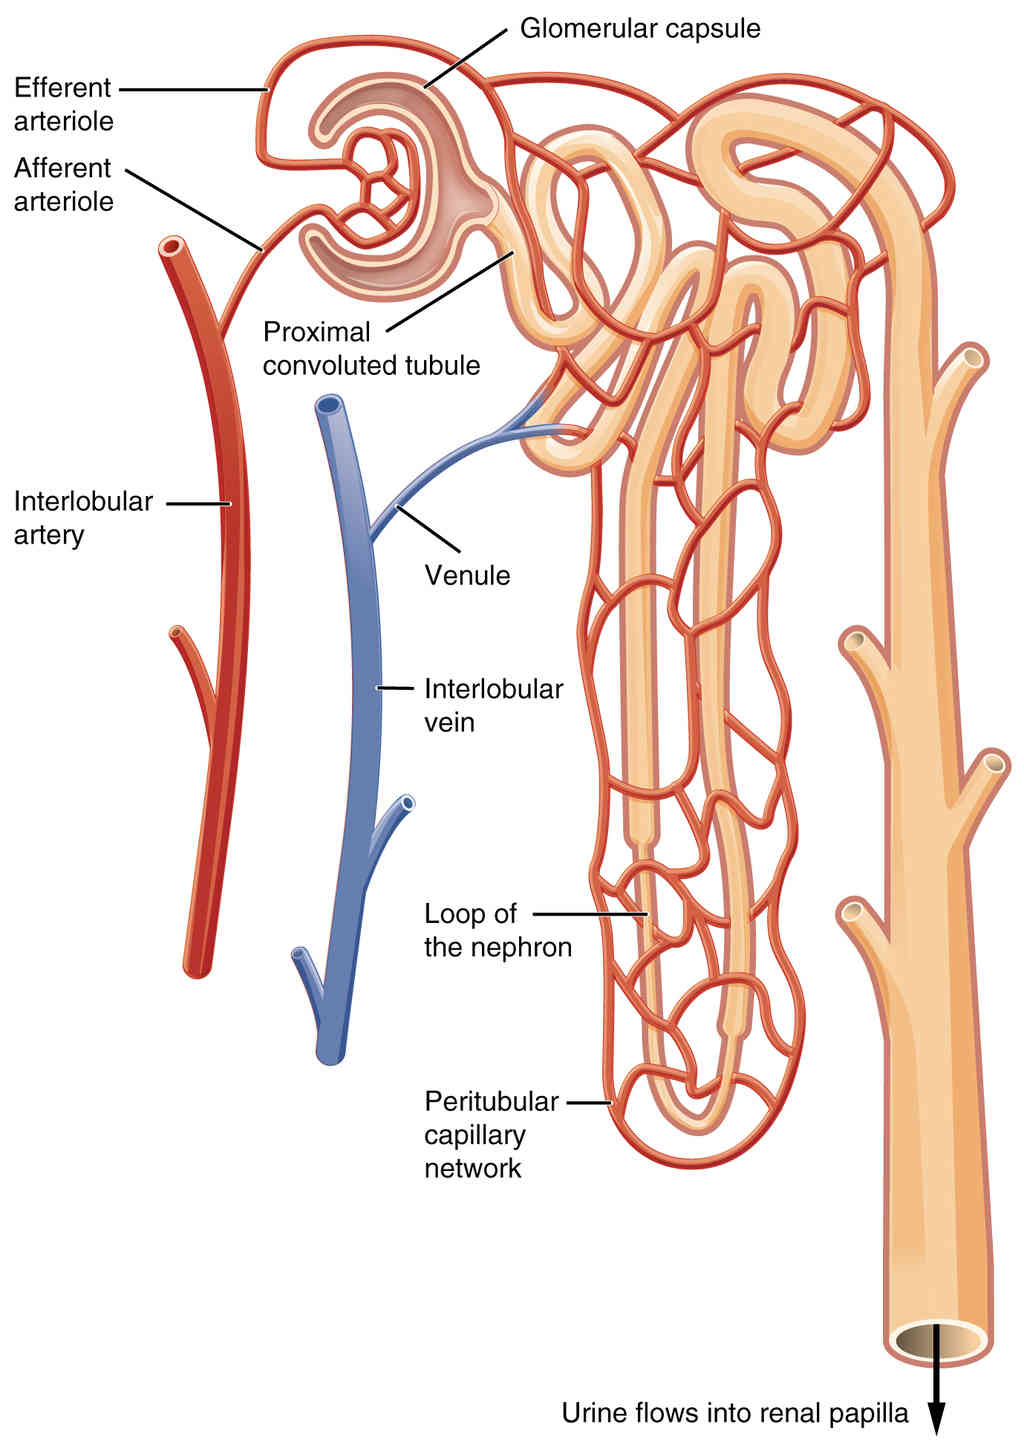

Anatomy, Physiology and Histology

This page is under construction. For now, it is just a resource of the images found in the OpenStax Anatomy and Physiology Handbook. It wil slowly change into a revision tool. Each slide has a number. Use this to refer to the slide. When completed, it will have an unlabelled section, with labelled slides in parallel. On the unlabelled slides, write your answer and use the labelled slide to assess yourself. Keep track by also noting the number on each slide. Improvement at each attempt is important, more so than full marks on a first attempt.